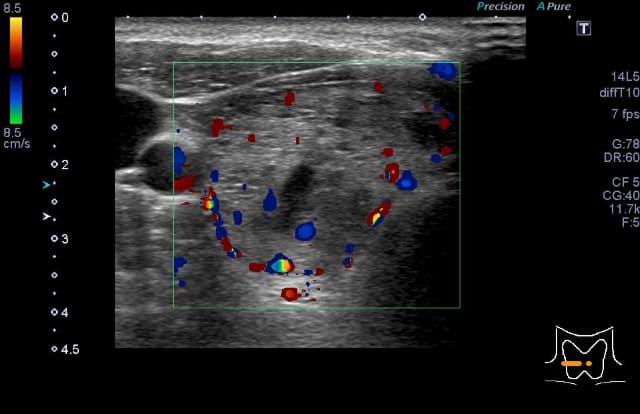

本症はバセドウ病と比べると、FT3/FT4比やFT4値が低かったり、TSH受容体抗体が陰性または低値のことが多く、甲状腺エコーで上甲状腺動脈の最高流速速度も低い、などの特徴があります。本症と診断された場合は、一般的にはバセドウ病のくすりは服用せずに経過観察をします。甲状腺ホルモンが過剰の時期から低下症の時期を経ますが、多くは2か月程度で正常に戻ります。低下症になってすぐには、低下症が継続するかの判断は難しく(抗甲状腺関連抗体陽性例では低下症継続の率が上がることは参考になります)、この時期で開始した補充療法は途中で中止できる可能性があります。

甲状腺超音波(エコー)検査では、甲状腺は基本的には全体的に大きくなり、内部は粗くみえることが多いです。臨床診断は、甲状腺の全体的な腫大に加えて、TgAbまたはTPOAb陽性で行います。甲状腺機能が正常であれば治療の必要はありません。機能が低下している場合には飲み薬(チラーヂンS®、レボチロキシン®)によって甲状腺ホルモンの補充を行います。服用は一日一回です。(吸収の安定性からは空腹時の服用がよく、また金属系製剤と同時服用は避ける必要があります)